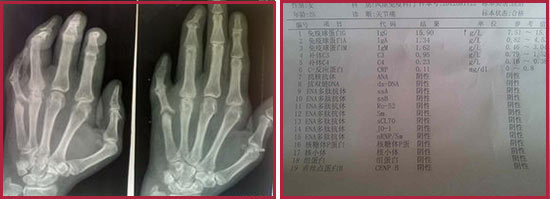

(图:类风湿性关节炎常规检查容易出现误诊漏诊的情况)

2、检查方法过于陈旧:由于一些临床医师缺乏对类风湿性关节炎特点的认识或只满足于X线检查,过分依赖骶髂关节的影像学检查,而忽视类风湿性关节炎的临床表现和体格检查,检查过于简单,无法科学的诊断病情,出现错误和遗漏,给治疗造成障碍。